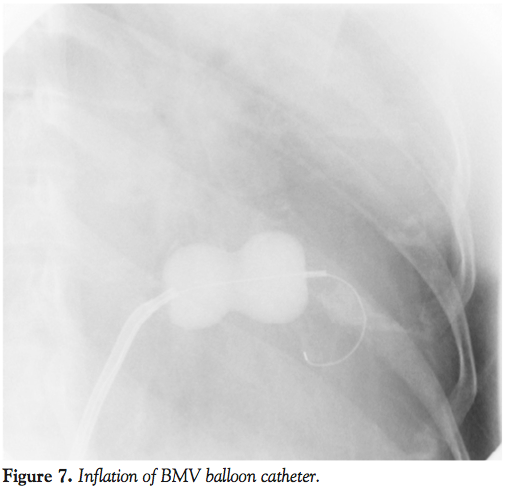

A 45-year-old woman presented with severe symptomatic mitral stenosis with mitral valve orifice area of 1.0 cm2 at cusp level and 0.4 cm2 at chordal level (Figure 1). The submitral apparatus was extensively diseased with thickening and fusion (Figure 2). Initially balloon mitral valvotomy (BMV) was attempted by over-the-wire technique described by the authors.1 In this technique, a deliberate low septal puncture is made and the 0.025-inch coiled guidewire is directly placed in the left ventricle (LV) (Figure 3).

The coiled guidewire was withdrawn and a 0.035-inch Terumo wire (Terumo Corporation) was introduced into LV with the support of a Judkins right catheter (Figure 5) and the distal end was parked in the right subclavian artery. An 8 x 20 mm Opta-Pro PTA balloon (Cordis Corporation) was passed over the Terumo wire and the submitral apparatus was serially dilated (Figure 6). The Terumo wire was then exchanged for a coiled guidewire and the procedure was completed with a BMV balloon catheter (Figure 7). The medial commissure was split (Figure 8) and the submitral stenosis was released (Figure 9).